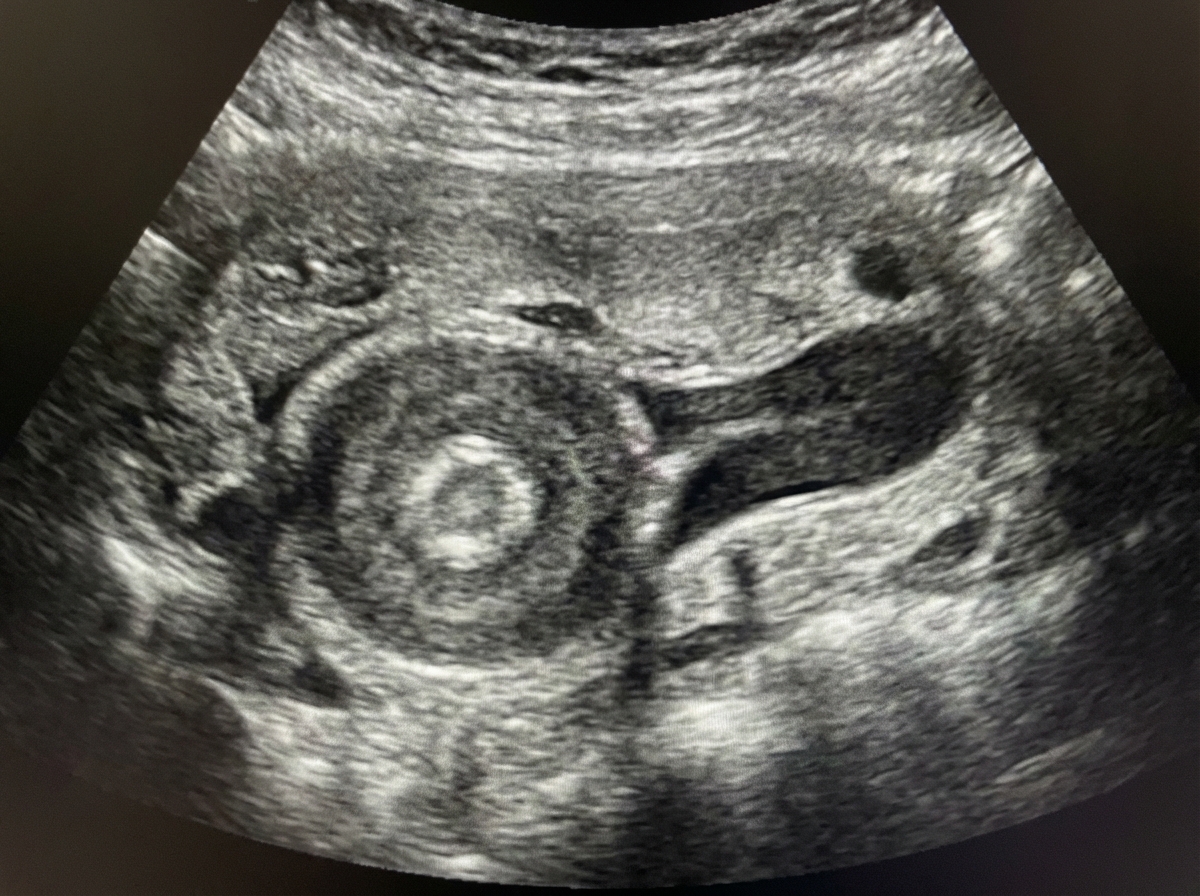

Explanation: ***Pyloric stenosis*** - A **6-week-old infant** with a palpable **epigastric mass** (olive-shaped) is classic for **hypertrophic pyloric stenosis**, which typically presents between 2-8 weeks of age. - Ultrasound shows the characteristic **"donut" or "target" sign**, and barium studies reveal the **"string sign"** due to narrowed pyloric channel. *Duodenal Atresia* - Presents in **neonates** (within first few days of life) with **bilious vomiting** and **"double bubble" sign** on X-ray. - Does not cause a palpable **epigastric mass** like pyloric stenosis does. *Choledochal cyst* - Typically presents with the classic **triad of jaundice, pain, and palpable mass**, but the mass is usually in the **right upper quadrant**. - More commonly diagnosed in **older infants** and children, not typically at 6 weeks of age. *Oesophageal Atresia* - Presents in **neonates** immediately after birth with **inability to swallow**, **excessive drooling**, and **choking** during feeding attempts. - Does not cause a palpable **abdominal mass** as it involves the esophagus, not intra-abdominal structures.